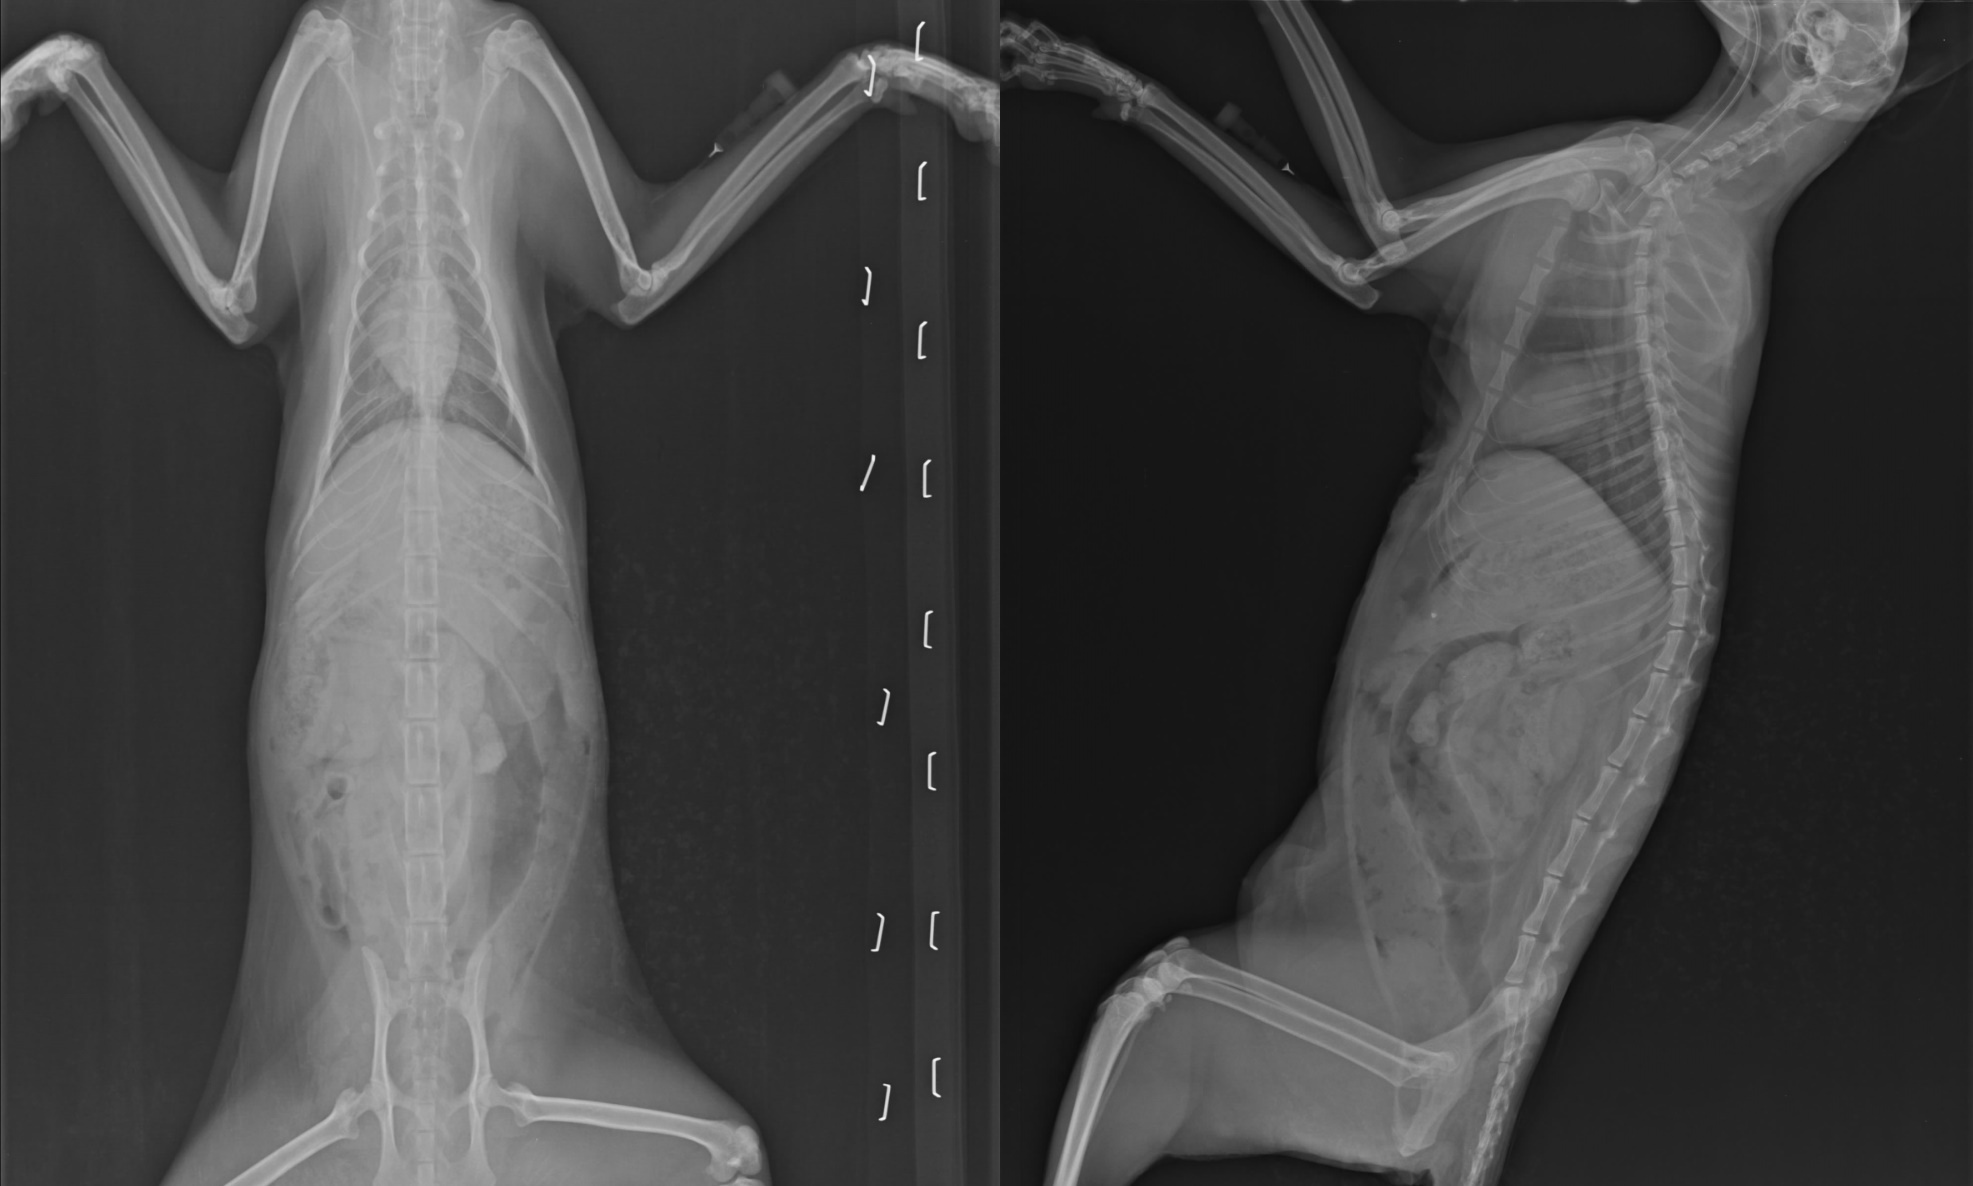

主題: 新店難產子宮脫垂黑母貓Y妹 申請者姓名: 臺北市支持流浪貓絕育計劃協會 花色: 申請日期: 2013-10-23 14:56:19 申請者部落格: 申請者臉書網址: 所在縣市/合作醫院: 台北市/極光動物醫院 治療費用: 25510元 需求人數: 27人 已結案 (2014-01-10 17:58:46) 報名人員: Avril Wang(已付款)、Jason x2(已付款)、Tina Ting(已付款)、坑長(已付款)、有貓真好(已付款)、Cathy Kao(已付款)、小貞(已付款)、Allen German x2(已付款)、susan(已付款)、王千枝(已付款)、Maureen Huang(已付款)、vivian(已付款)、王可樂的日語教室(已付款)、Mia Jheng(已付款)、陳又寧(已付款)、Yi-Jun Huang(已付款)、Yi-Jun Huang(已付款)、Ava(已付款)、Larry Shen(已付款)、sharon1161(已付款)、Kuen-Lin Tsai(已付款)、小娃(已付款)、Show(已付款)、小小瑋(已付款)、壹零(已付款)、 候補人員: 動物病情說明: 新店愛媽電話至協會,餵養的貓難產,星過一周時間,母貓陰道口還有二支東西露出外面,愛媽說是小貓的腳,前去誘捕,晚上順利抓到,送醫後,是子宮斷裂,脫垂出來,母貓命大,竟然還能活下來!

術後恢復狀況良好,但白血球36700有感染的狀況,還需要抗生素治療,所幸感染得以控制,現已經康復本來預計要R回,但愛心媽媽住院無法照顧,暫時安置協會。